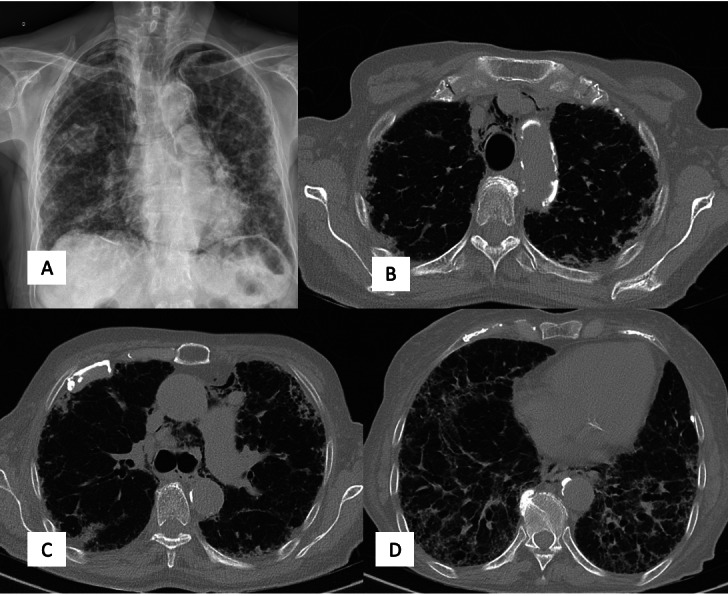

Clinical case: 76-year-old patient with pre-existing diffuse interstitial lung disease, who experienced a massive stroke due to spontaneous pneumomediastinum. Her presentation included confusion, seizures, and motor weakness. Imaging tests revealed air bubbles in the cerebral sulci and hypodense areas in the cerebellum and parietooccipitals. In addition, pneumothorax and air in the upper mediastinum were noted on chest radiographs and chest CT scan. Despite therapeutic measures such as hyperbaric oxygen, the patient unfortunately died due to multiple organ failure.